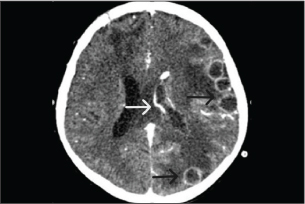

On day 28 of combination antifungal therapy, the patient experienced a severe left temporal headache accompanied by motor weakness (grade III on the right side and grade IV on the left side). Repeat brain CT demonstrated progression of abscesses, left lateral ventriculitis, increased vasogenic edema, and uncal herniation (Fig. 4). The patient was deteriorating, and there was significant brain swelling. A third neurosurgical intervention involving left decompressive craniectomy with duraplasty and EVD placement was performed to relieve intracranial pressure. Postoperatively, the patient showed slight improvement in motor function and maintained normal consciousness.

Fig. 4. A computed tomography scan of the brain with contrast on day 28 of antifungal treatment showed increased size of some abscesses (white arrow), ventriculitis of the left lateral ventricle, increased vasogenic edema, and midline shift to the right (black arrow).